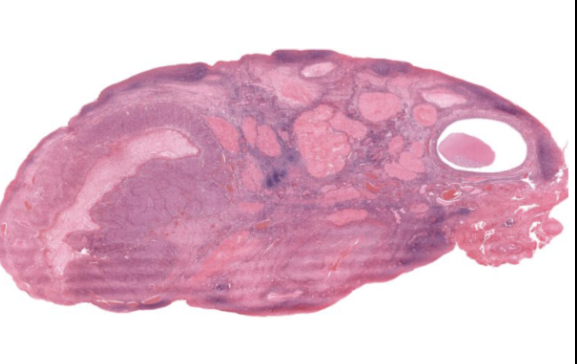

OVARY: Outer cortex, containing follicles at varying stages

Inner medullary region, ovarian artery and veins

simple cuboidal on ovarian surface epithelium in outer cortex

Has basement membrane and DIRCT below as tunica albuginea

Corcles are follicles at varying stages of development

Cortex contains follicles